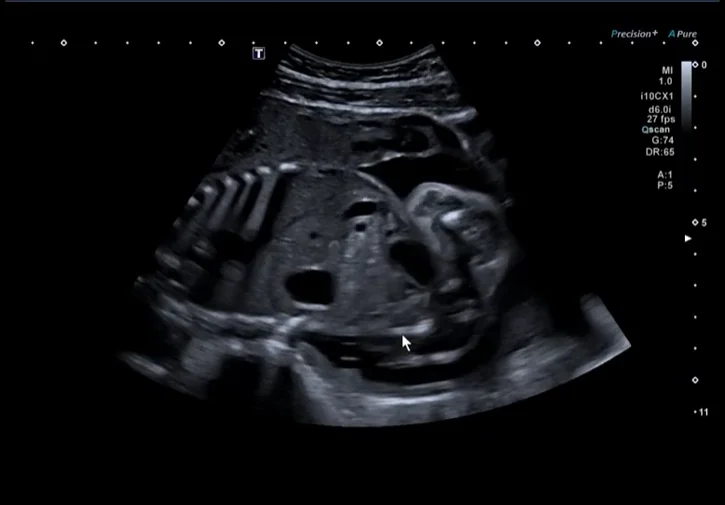

Nhiễm trùng thai

Tiếp cận nhiễm trùng bào thai (Fetal Infection)